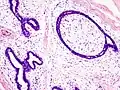

| Histopathologic image of breast fibroadenoma. Core needle biopsy. H&E stain. | |

Fibroadenoma of the breast is a benign tumor composed of a biplastic proliferation of both stromal and epithelial components.[12][13] This biplasia can be arranged in two growth patterns: pericanalicular (stromal proliferation around epithelial structures) and intracanalicular (stromal proliferation compressing the epithelial structures into slit-like spaces).

These tumors characteristically display hypovascular stroma compared to malignant neoplasms.[2][14][9] Furthermore, the epithelial proliferation appears in a single terminal ductal unit and describes duct-like spaces surrounded by a fibroblastic stroma. The basement membrane is intact.[15]

Fibroadenoma histology (H&E). The image demonstrates intracanalicular morphology (bottom left) and pericanalicular morphology (top right) -

Histopathologic image of breast fibroadenoma. Core needle biopsy. Hematoxylin & eosin stain. -

Histopathologic image of breast fibroadenoma showing proliferation of intralobular stroma compressing and distorting the epithelium. H&E stain. -